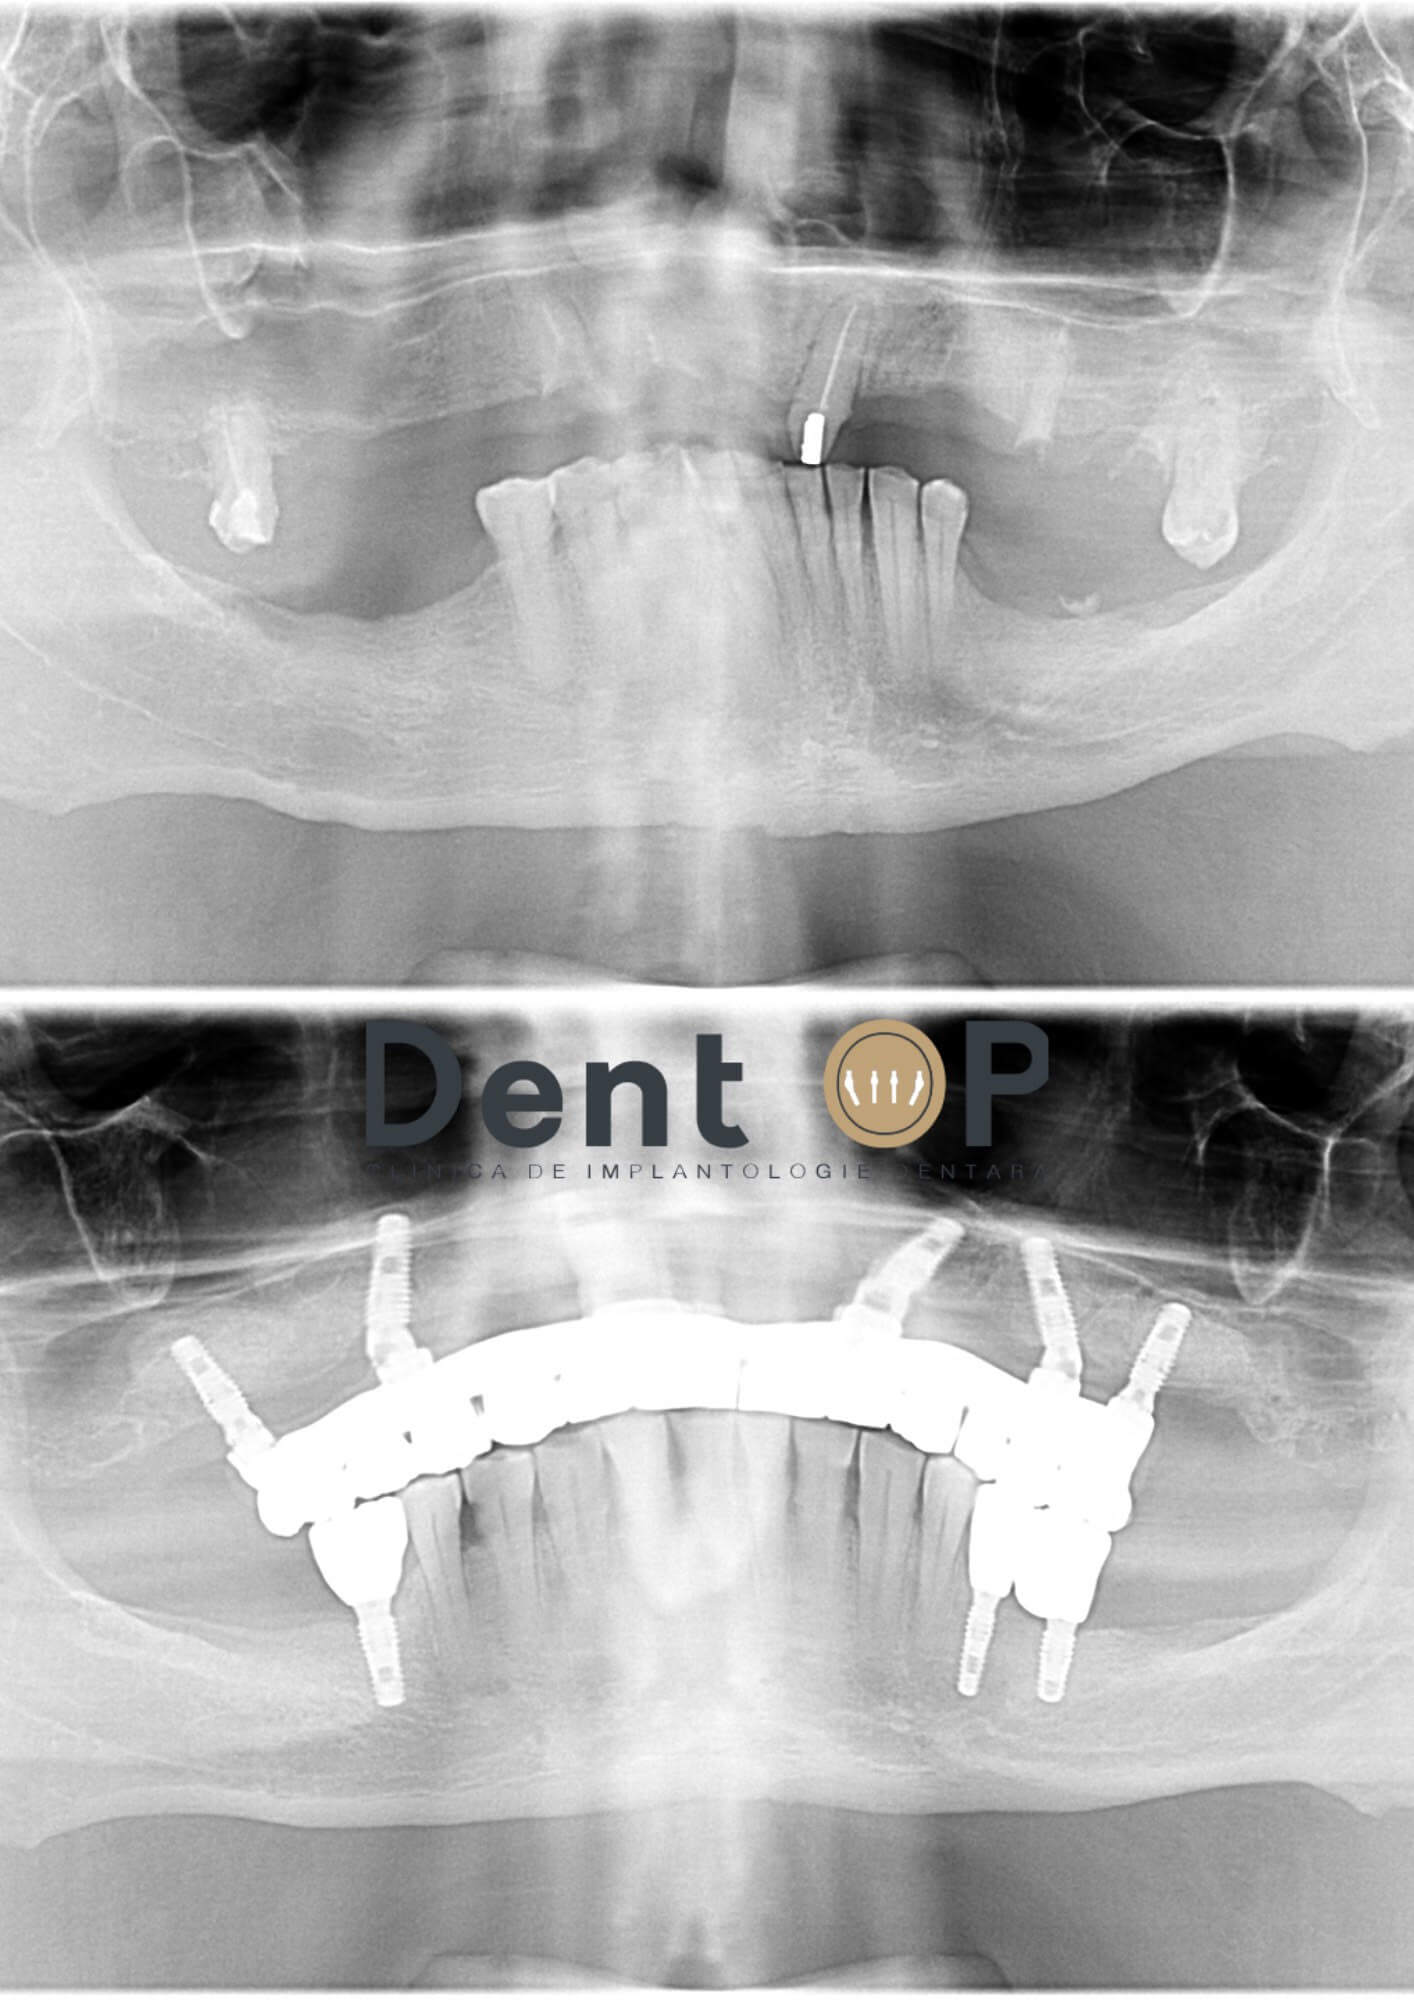

Dr Cazacu Corrado i-a propus un plan de tratament predictibil în urma consultației care a inclus inserarea a 9 implanturi dentare. Acestea au fost distribuite astfel : 6 la maxilar (pentru a realiza o dantură fixă) și 3 la mandibulă în poziții cheie pentru a completa dantura. Dinții care au putut fi salvați au fost păstrați.

În radiografia de mai jos vom putea observa cum arată dantura domnului S. înainte și după inserarea implanturilor dentare.